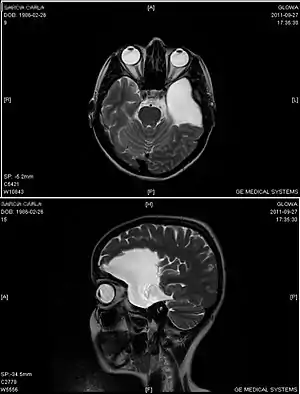

| An MRI of a 25-year-old woman with left frontotemporal arachnoid cyst. | |

Diagnosis is principally by MRI. Frequently, arachnoid cysts are incidental findings on MRI scans performed for other clinical reasons. In practice, diagnosis of symptomatic arachnoid cysts requires symptoms to be present, and many with the disorder never develop symptoms.